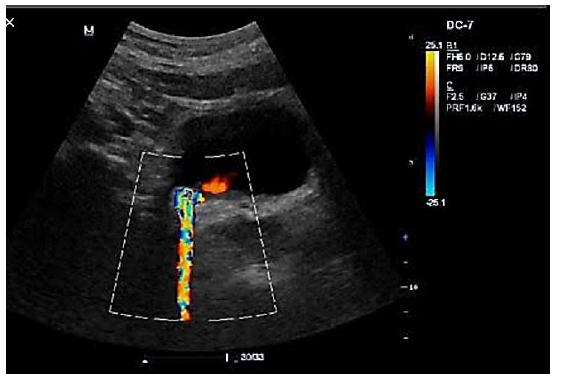

Com base nas imagens, assinale a artéria que está sendo estudada e a conduta esperada.